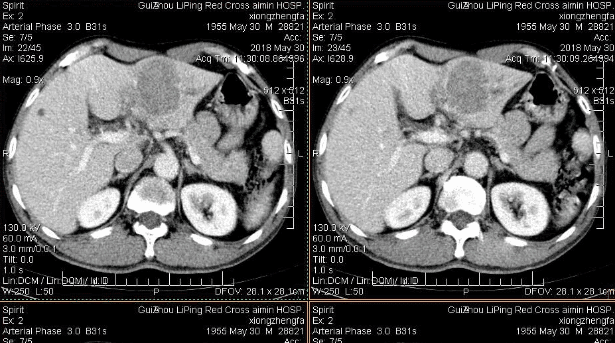

上个月 , 两人用辛辛苦苦打拼攒的钱买了一套属于他们自己的爱巢 , 正要庆祝 。 可是人有旦夕祸福 , 本月月初 , 妻子在年中公司体检中查出了肝硬化 , 顿时 , 整个家庭被笼罩在阴影之下 。

才25岁的女孩为何会被查出肝硬化呢?

据医生了解后发现 , 原来李军和他的妻子因生活压力所致 , 一直不想要孩子 , 想经济基础牢靠再要孩子 。

但是生活需要调剂 , 身体需要释放 。 因此 , 夫妻二人在行房事之时 , 通常会戴安全套 , 但是太过麻烦 , 就索性妻子长期吃避孕药以避免怀孕 。

可谁能想到正是长期吃避孕药导致妻子患肝硬化!

长期服用避孕药 , 会引发药物性肝损伤 , 具体表现为肝窦扩张、肝细胞纤维化 , 甚至形成肝小静脉阻塞等后果 。